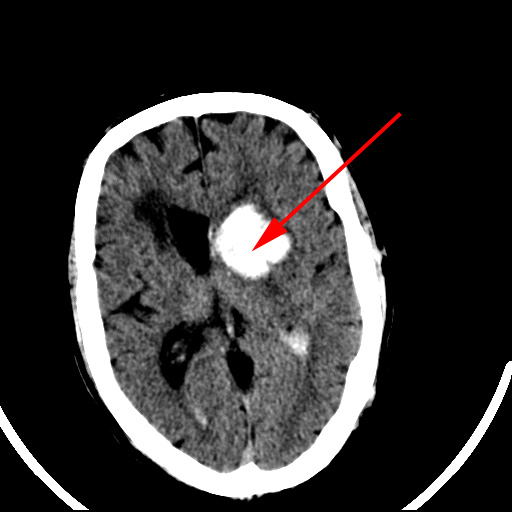

CT-skanning af cerebrum der viser en frisk blødning i hjernen (rød pil) hos to forskellige patienter.